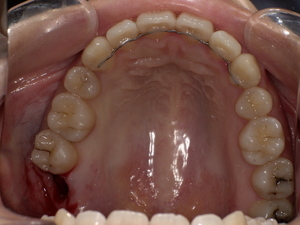

口の中のどこにできる?(舌・頬・歯茎など)

頬の内側:もっとも一般的。

舌の横や裏:白斑が見られやすいです。

歯茎や唇の裏:発生することもあり、視認しづらいため注意が必要。

口蓋(上顎内側):稀に見られる部位。